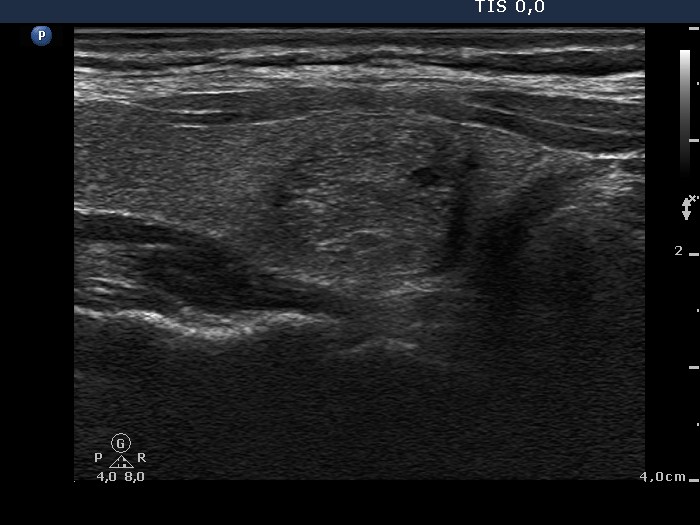

Ultrasonography: there was a minimally-moderately hypoechogenic nodule in the right lobe. The lesion contained tiny, hyperechogenic granules. A type 3 vascular pattern.

It is worth analyzing the hyperechogenic foci within the lesion. The tiny granules are more probably presentations of fibrosis than that of microcalcifications.